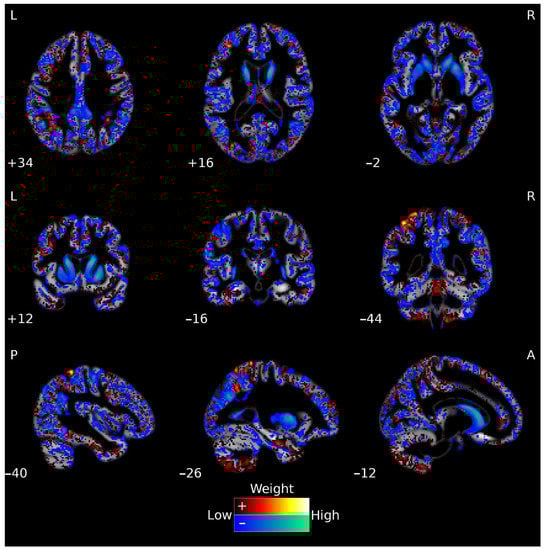

3.3. FA Classification

3.4. Multimodal Neuroimaging Classification